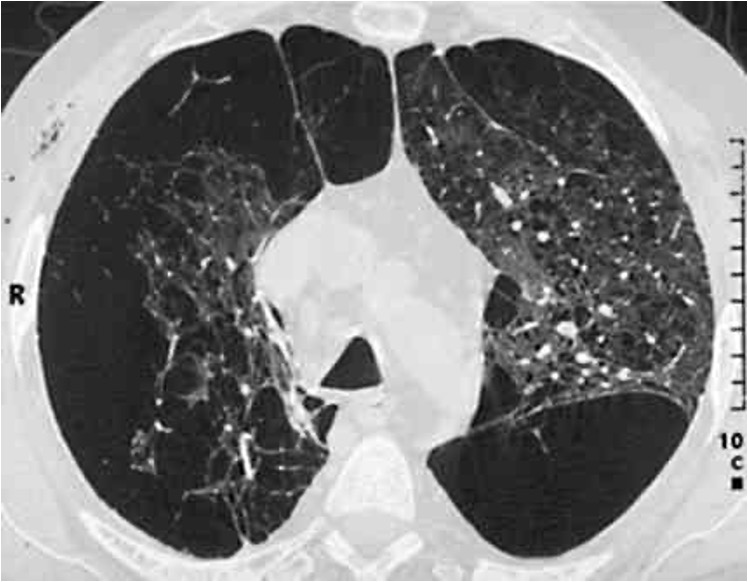

Abb. 1: Röntgenaufnahme des Brustkorbs. Frontalebene (a.p.-Aufnahme). Der weiße Pfeil markiert einen Lungen-leeren rechten Brustkorb (Patienten-rechts, links im Bild) in Folge eines Pneumothorax (Luft im Brustkorb). Hier zeigt sich kein Lungengewebe im Vergleich zur Gegenseite (Patienten-links, rechts im Bild). © Dr. Dr. Philipp Stahl

Eine Zusammenfassung zur COPD und Tauchsport gibt Info-Box III. Neben häufig bestehenden Komorbiditäten (Begleiterkrankungen) bei Patientinnen und Patienten mit COPD, wie Herz-Kreislauf- und Gefäßerkrankungen sowie Diabetes mellitus, welche die körperliche Leistungsfähigkeit und damit die Fähigkeit zur Erlangung einer Tauchtauglichkeit einschränken, bestehen erhebliche Gefahren beim Tauchen bei fortgeschrittenen Stadien dieser Lungenerkrankung. Hier ist vor allem die erhöhte Gefahr  eines Pneumothorax (Lungenriss) zu nennen, der durch die überblähten Lungenbereiche (Lungenemphysem) in der Dekompressionsphase entstehen kann (Abb. 1). Prinzipiell ist der Pneumothorax auch bei nicht vorbestehendem Lungenemphysem bei der COPD analog zum Asthma bronchiale durch Air trapping und der dafür bereits aufgeführten Risikofaktoren möglich.